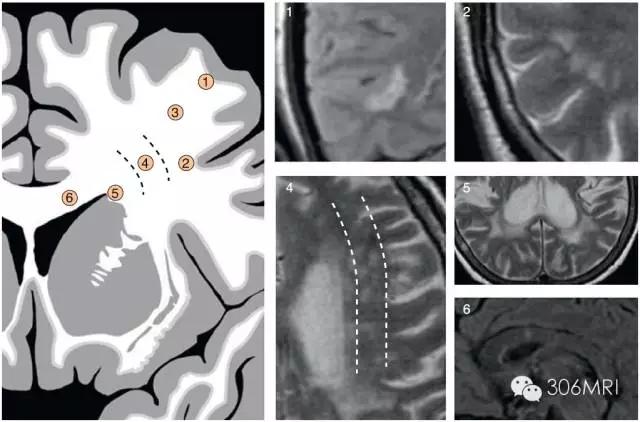

对于白质区内斑点灶的识别与临床意义所在,有国外学者将白质区域及常见的斑点影像通过画图方式进行了归纳与展示,看到这些,我的膝盖碎了!

部位: ①皮质旁; ②皮层下U型纤维; ③皮层深部非边缘区; ④皮层下边缘区; ⑤脑室旁; ⑥胼胝体。

主要累及皮层旁①/或者胼胝体⑥提示是非血管性模式,其余部位趋于血管性模式或者非特异性模式,提示小血管病因。脑室周围病变取决于病变形状而可能提示血管性模式或者血管周围模式。

常见斑点影形状及发生部位与意义

血管性模式提示为微血管病灶,多指小动脉闭塞;血管周围模式主要提示脱髓鞘病变,如多发性硬化(MS);非特异性模式提示小血管病可能。

将斑点形状与部位归纳入三种不同的基本模式,其意义分别表示:血管性模式-多由小动脉病变引起,最普遍;血管周围模式-血管周围感染性病变引起,是相比少见的病因。典型者是多发性硬化MS,小静脉周围自身免疫性感染引起脱髓鞘;非特异性模式-多由小血管疾病引起。